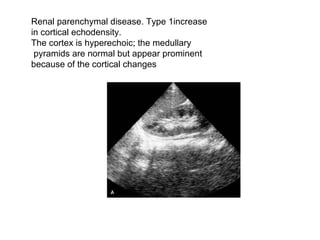

Renal parenchymal disease. Type 1increase  in cortical echodensity.  The cortex is hyperechoic; the medullary pyramids are normal but appear prominent  because of the cortical changes